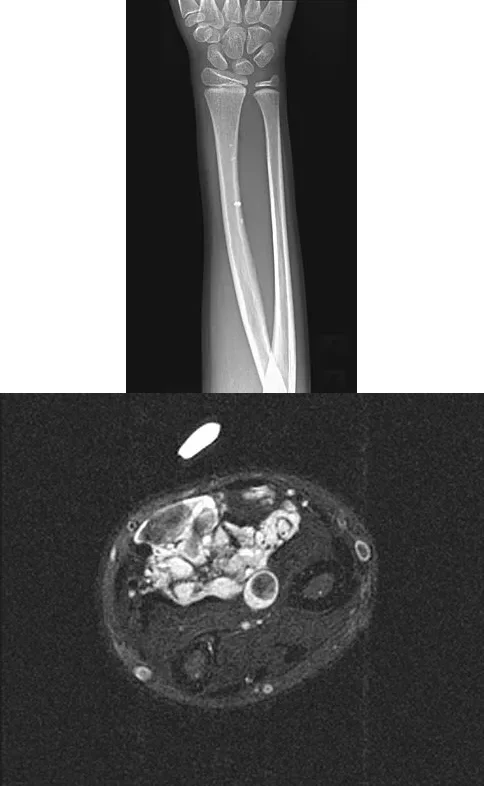

A 64-year-old woman sustains the wrist injury shown in the radiographs. The injury is a volar displaced intra-articular distal radius fracture. When utilizing a volar buttress plate for this specific fracture pattern, what is the primary biomechanical function of the plate?

Explanation

Correct Answer: C

The radiographs show a volar Barton's fracture (volar displaced intra-articular fracture of the distal radius). The primary deforming forces are axial loading and volar shear, which cause the carpus to subluxate volarly with the fracture fragment. A volar buttress plate is applied to physically block (buttress) this volar displacement, neutralizing the axial and shearing forces.

A 64-year-old woman sustains the wrist injury shown in the radiographs after a fall on an outstretched hand. The fracture pattern involves a volar displaced intra-articular fragment. What is the primary biomechanical rationale for utilizing a volar buttress plate in the surgical management of this specific injury?

Correct Answer: It neutralizes axial loading forces on the fractured volar fragment.

The radiographs demonstrate a volar Barton's fracture, which is a volar displaced intra-articular fracture-dislocation of the distal radius. The volar carpal ligaments remain attached to the volar fragment, pulling the carpus volarly. A volar buttress plate is biomechanically ideal for this injury because it acts as an anti-glide plate, neutralizing the axial loading and shear forces that drive the fragment proximally and volarly. A dorsal plate would not provide this buttress effect and would make maintaining the reduction difficult.